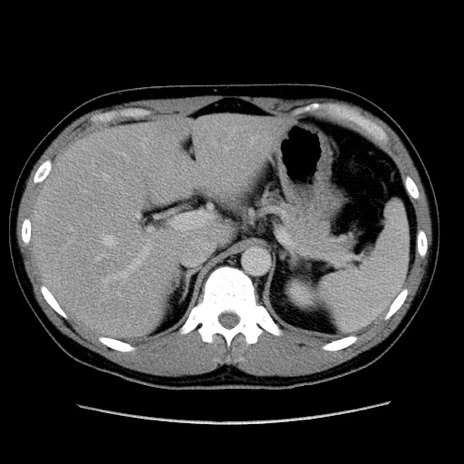

症例4(横断像)

【症例】30歳代男性

【主訴】腹痛、嘔吐

【現病歴】昨晩から突然の腹痛あり、その後嘔吐、軟便も出現。腹痛が改善しないため救急搬送となる。2日前にしめ鯖の食事歴あり。

【身体所見】意識清明、苦悶様、BP 135/90mmHg、BT 35.7℃、腹部:平坦、やや硬、心窩部〜臍部に自発痛、圧痛あり、筋性防御+、反跳痛-

【データ】WBC 8100、CRP 0.57